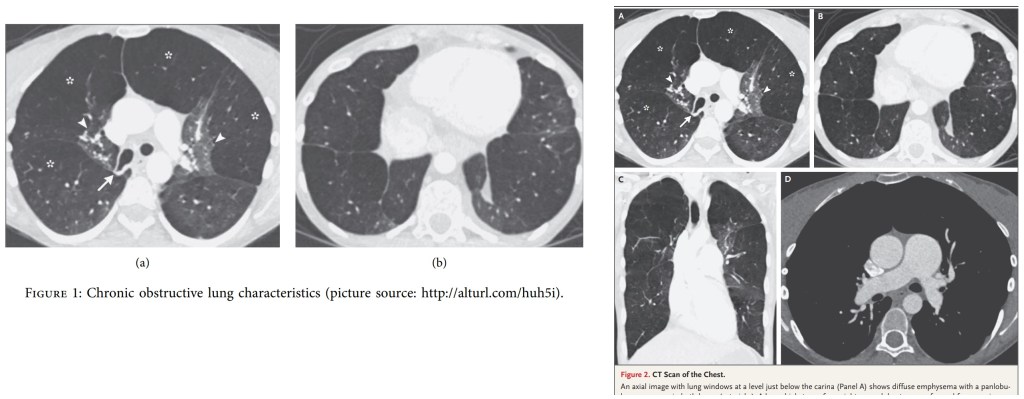

I am not detecting a great deal of pride in workmanship. Another example? Fig 1 of Xie et al (2021), “Chronic obstructive lung characteristics”, turns out to be sourced from “Case 28-2019: A 22-Year-Old Woman with Dyspnea and Chest Pain“… though filtered through a series of Chinese websites. While on close inspection of Fig 6, “The current quality of life of COPD patients at different stages of pulmonary rehabilitation exercise behavior”, the panels turn out to be not directly lung-related, but MRI-scan slices of a massive cerebral hemorrhage. Happily, the 73-year-old patient was saved by prompt craniectomy and decompression. The putative authors do warn us that “No data were used to support this study”.